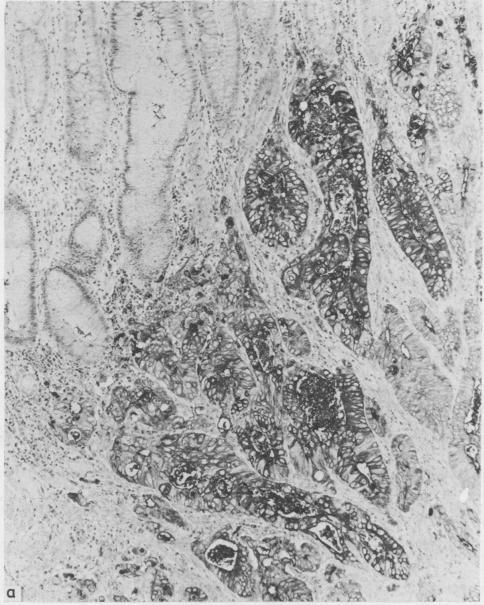

An immunoperoxidase technique was applied to formalin and Helly fixed paraffin wax sections from cases of ulcerative colitis complicated by dysplasia and carcinoma for carcinoembryonic antigen and components of the colonic secretory immunoglobulin system--namely, secretory component, IgA, and J chain. Sections from both resection specimens and mucosal biopsies were available. Intensity of immunostaining was assessed qualitatively. There was appreciable variation in expression of carcinoembryonic antigen and secretory component antigens. Carcinoembryonic antigen stained heavily in dysplasia and carcinoma while these tissues showed only focal light staining for secretory component. Normal tissue stained heavily for secretory component. The variation in staining intensity for both carcinoembryonic antigen and secretory component in inflamed and regenerative mucosa precluded their use as a reliable diagnostic aid in discriminating these tissues from true dysplasia. Loss of secretory component production or transport or both may be incurred during malignant change, but it should not be assessed as an isolated index of epithelial maturity. The relation with mucosal plasma cells warrants further study to determine more fully the factors affecting tissue secretory component expression.

免疫过氧化物酶技术应用于福尔马林和Helly固定的石蜡切片,这些切片取自溃疡性结肠炎并发发育异常和癌的病例,用于检测癌胚抗原和结肠分泌型免疫球蛋白系统的成分,即分泌成分、IgA和J链。切除标本和黏膜活检的切片均可用。免疫染色强度进行定性评估。癌胚抗原和分泌成分抗原的表达存在明显差异。癌胚抗原在发育异常和癌组织中染色较深,而这些组织中分泌成分仅呈局灶性淡染。正常组织分泌成分染色较深。炎症和再生黏膜中癌胚抗原和分泌成分染色强度的变化,使其无法作为区分这些组织与真正发育异常的可靠诊断辅助指标。恶性改变过程中可能会出现分泌成分产生或运输或两者的丧失,但不应将其作为上皮成熟度的单一指标来评估。与黏膜浆细胞的关系值得进一步研究,以更全面地确定影响组织分泌成分表达的因素。